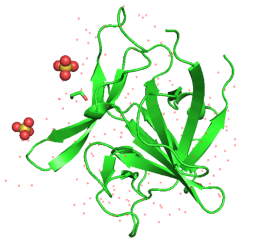

解析IL-1β与药物的复合物结构对于开发相关靶点药物具有重要意义。青云瑞晶参考PDB: 2NVH文献中的方法,针对IL-1β完成了117-269区域蛋白的表达、纯化和结晶,建立了高表达量、高纯度的表达纯化方案;对IL-1β(apo)晶体的多轮优化,得到了最佳的结晶条件,针对该靶点累积了丰富的数据。同时储备了IL-1β参与的上下游相关靶点蛋白的表达、纯化和结晶经验,满足企业药物研发需求。(uniprot: P01584)

图3. 基于结合配体的IL-1β-IL-1RI和IL-1Ra-IL-1RI在IL-1β-IL-1RII-IL-1RAcP上的叠加

▶结晶和结构解析(周期:1-2周)